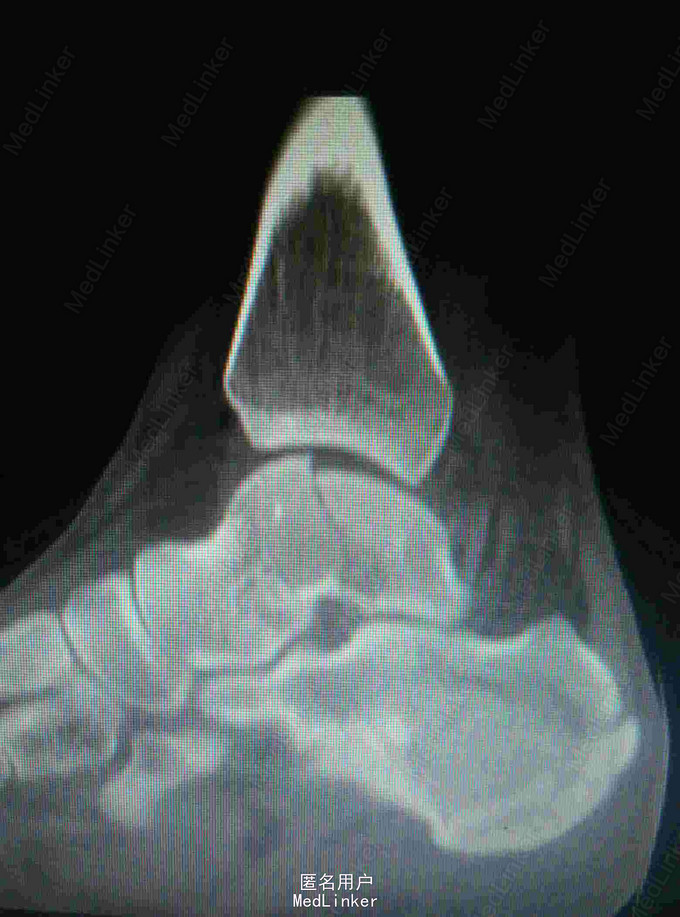

距骨骨折采用外踝截骨入路显露固定手术

患者,男,27岁,高处坠落致左踝部肿痛,活动受限

完善X线片及CT扫描检查